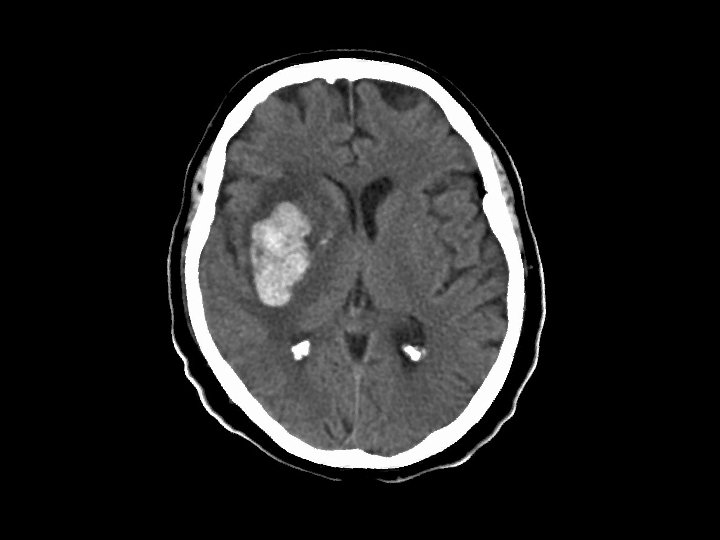

MCA hemorrhagic infarction • Findings: – Large hemorrhage in the right insula – Much surrounding edema – Some mass effect • Due to M 1 segment embolus affecting lateral lenticulostriate arteries • ddx: – Hypertensive hemorrhage (usually little or no edema) – Underlying tumor or AVM (need angio to confirm)